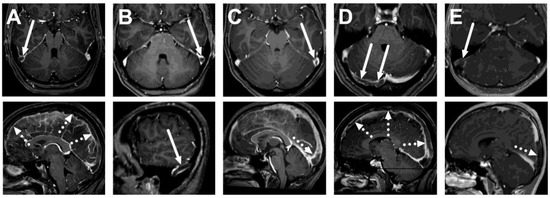

Figure 2.

An example of cerebral venous sinus thrombosis on routine pre-contrast images. Images show a lack of normal flow void on T2-weighted (A) and fluid-attenuated inversion recovery (FLAIR) (B) images, as well as high signal on the pre-contrast T1-weighted image (C), in the superior sagittal sinus (arrows). Post-contrast T1-weighted image is provided for reference (D), showing the non-enhancing thrombus (arrow). Most patients did not show thrombosis on all routine sequences, however. The patient is the same as in Figure 1C.